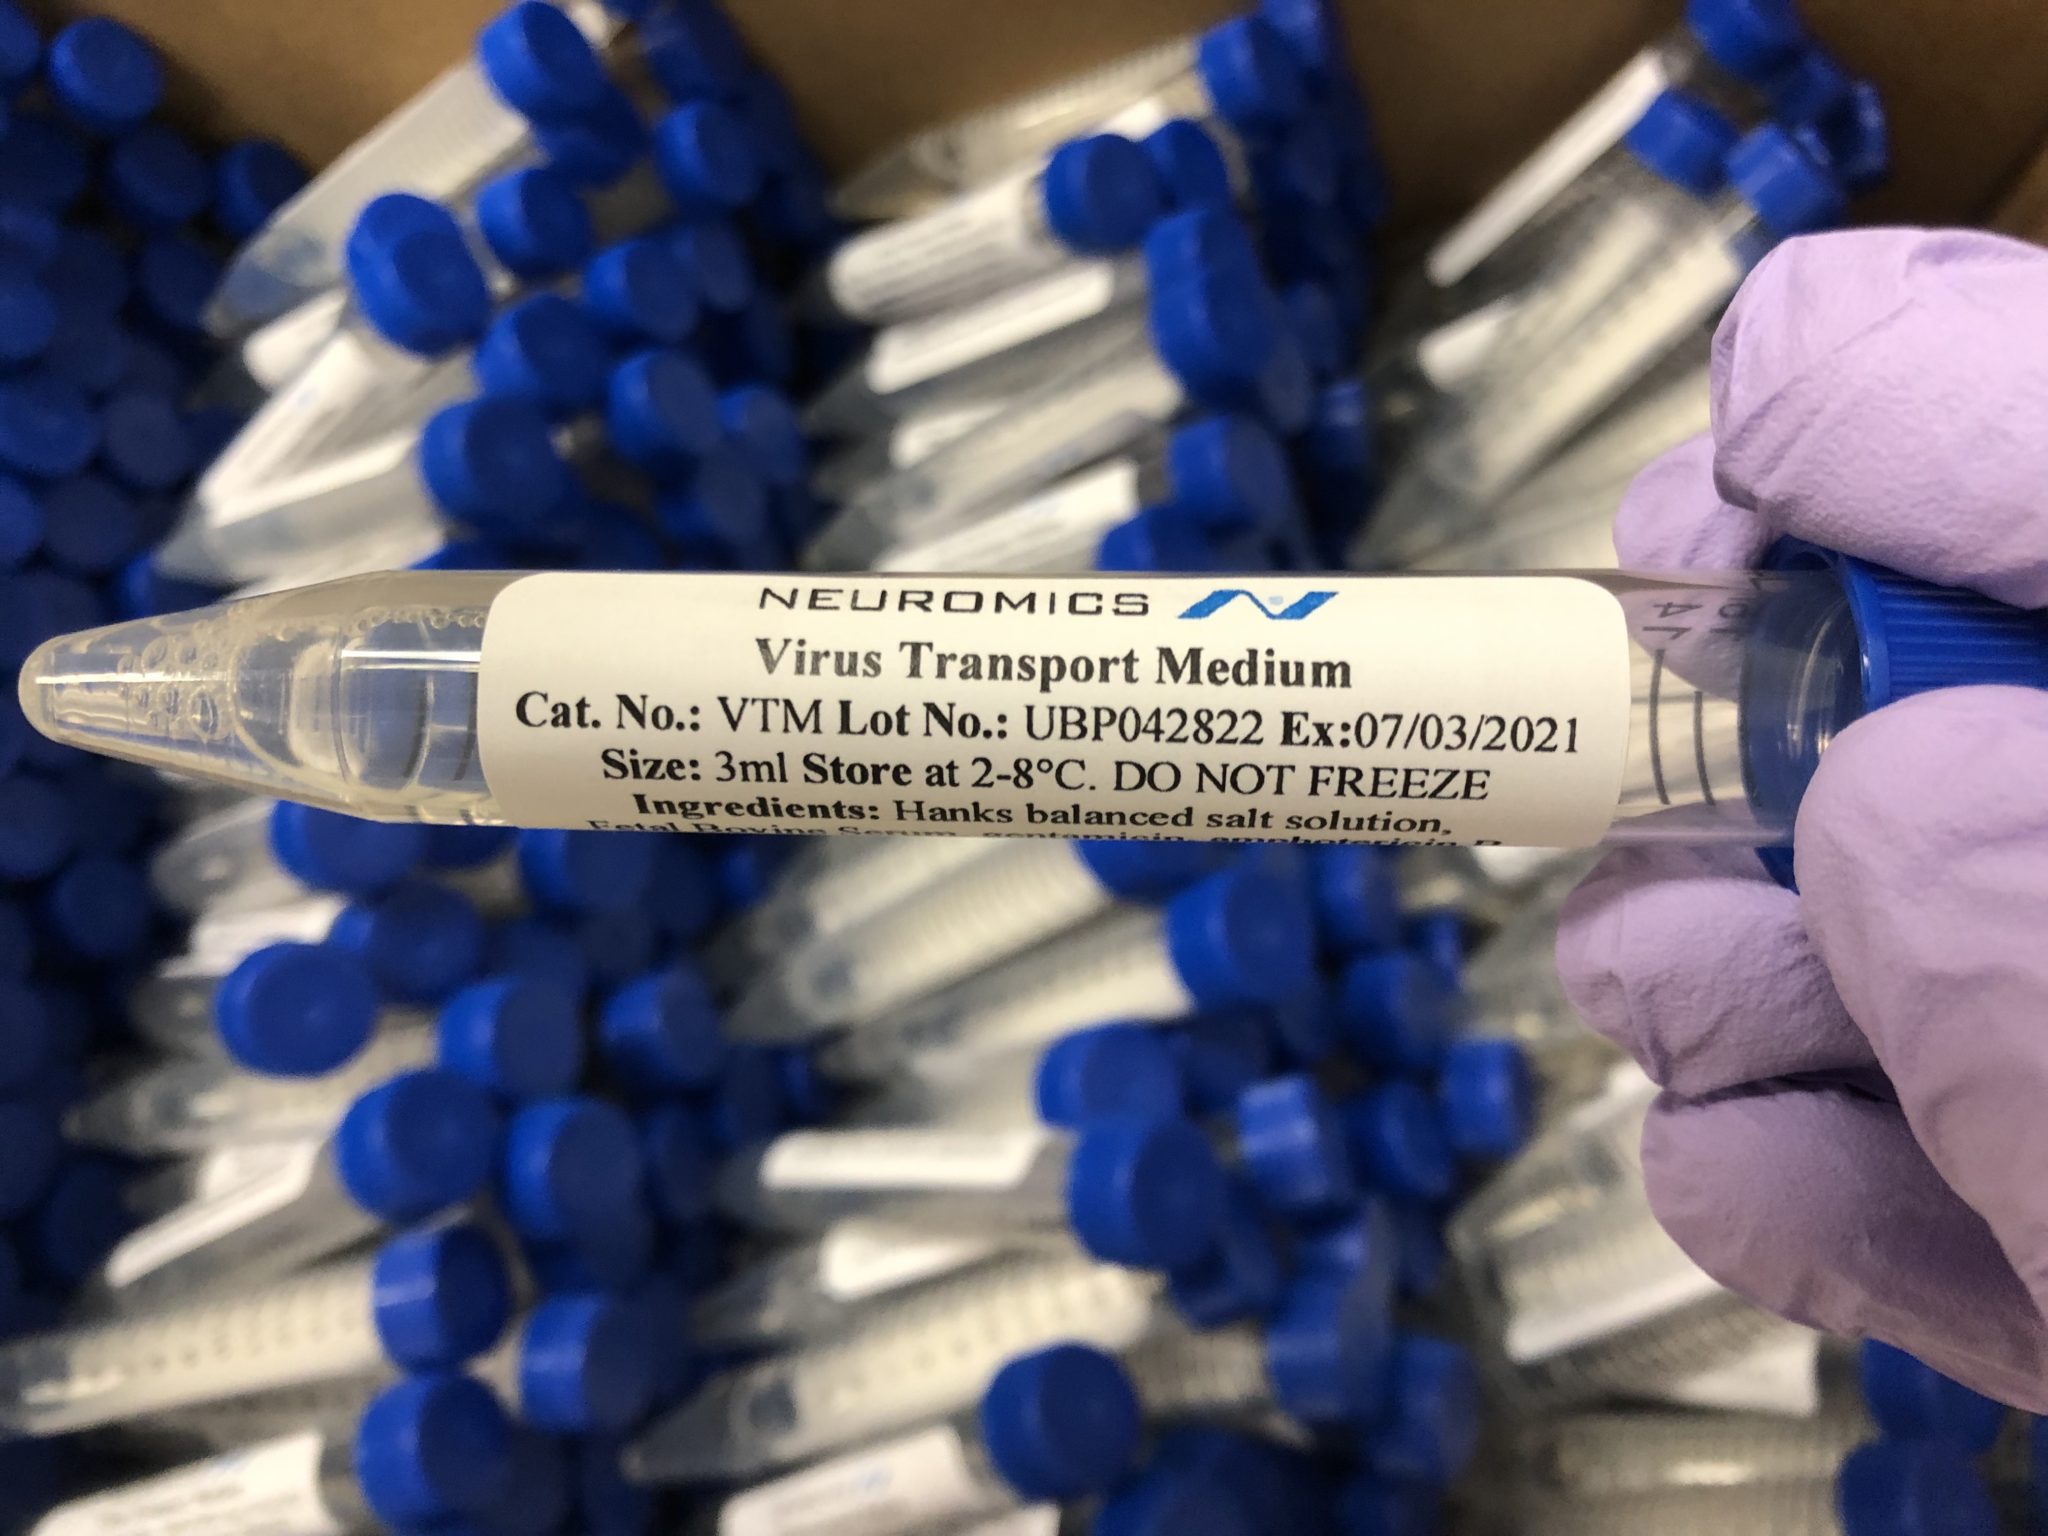

Neuromics has a wide variety of products to help researchers in their pursuit of finding answer on the COVID-19 virus. Additionally, we offer a selection of products that can be used in the COVID-19 testing process, including Virus Transport Media made in the United States.

Neuromics offers various products that can be used in COVID-19 testing, including Virus Transport Media, nuclease free water, and saline solutions.

Our virus transport media is designed to transport viruses, including COVID-19, for research and testing purposes. Using our high quality FBS, each lot of virus transport media (VTM) is manufactured in the United States under strict guidelines (see formulation) as outlined by the CDC, is sterile, and undergoes quality control before release. Furthermore, our VTM is available in both tubes, kits (include sterile swabs), or bulk quantities, allowing us to meet the needs of all types of buyers.

CDC Compliant Virus Transport Media and Kits

| Name | Catalog # | Size |

| Virus Transport Media | VTM | VTM-2: 3 ml VTM in 15 ml tube |

| Virus Transport Media | VTM | VTM-3: 50 ml |

| Virus Transport Media | VTM | VTM-4: 100 ml |

| Virus Transport Media | VTM | VTM-5: 500 ml |

| Virus Transport Media | VTM | VTM-6: 1000 ml |

| Virus Transport Media with Swabs | VTM-Kit | VTM-Kit: Tube w/ 3 ml VTM, sterile swab, bhz bag (min. 100) |

| Virus Transport Media with Swabs | VTM-Kit | VTM-with-Swab: 12 ml tube with 3 ml VTM and sterile swab |

As the COVID-19 pandemic continues to affect lives everywhere across the globe, Neuromics has begun to manufacture Molecular Transport Media (MTM). For the next few months, we will be filling hundreds of thousands of tubes with MTM to be used in COVID-19 testing.

This new media deactivates the COVID-19 virus and extracts its genetic material for simple PCR diagnosis.

We’d like to say a big thank you to our team for working around the clock to get MTM production up and running.

In addition to MTM, we continue to manufacture Virus Transport Media. Currently, we have up to 50,000 15 ml tubes with 3 ml VTM available. Email us at technical@stratech.co.uk if you have any need for a transport media.